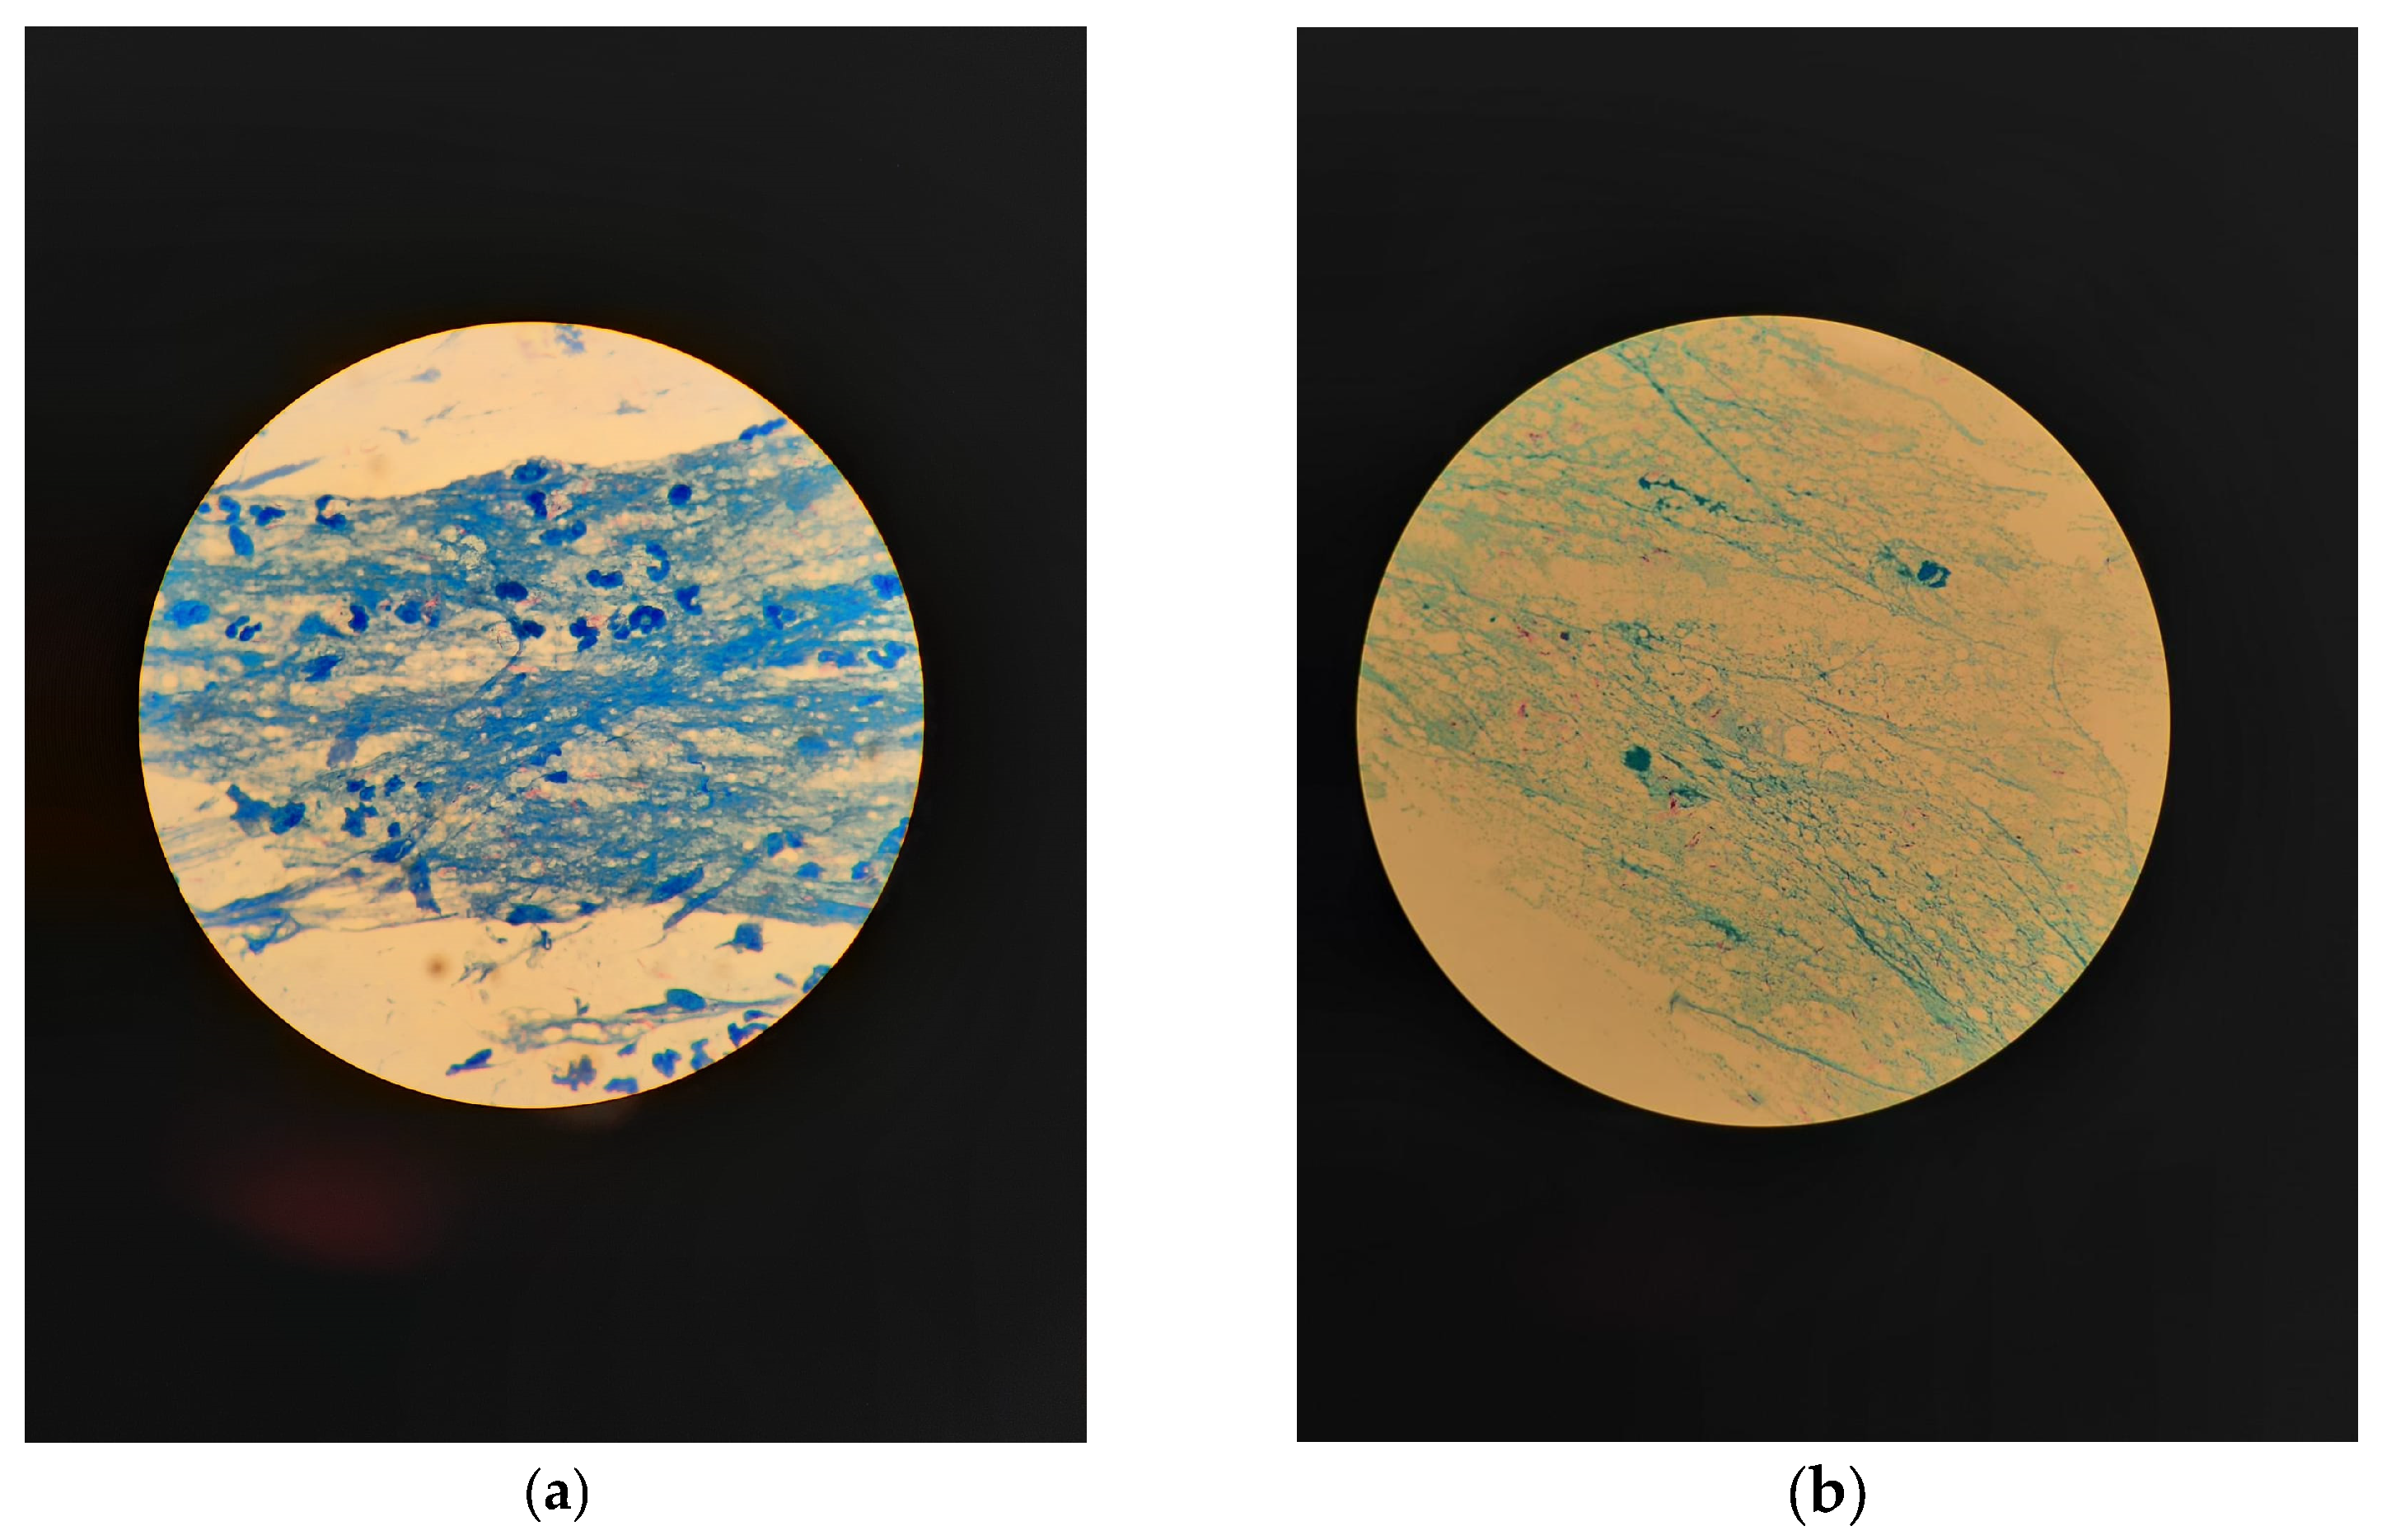

2. Microscopic Diagnosis of TB

2.1. Microscopic Examination with Ziehl–Neelsen Staining

2.2. Microscopic Examination with Fluorescent Staining